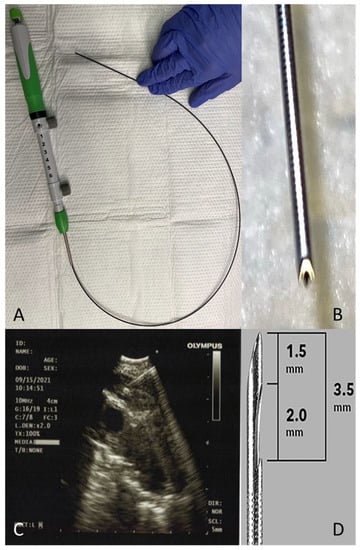

2.5. Core Needle

2.7. Lymph Node Cryobiopsy under EBUS Guidance

- Gonuguntla, H.K.; Shah, M.; Gupta, N.; Agrawal, S.; Poletti, V.; Nacheli, G.C. Endobronchial ultrasound-guided transbronchial cryo-nodal biopsy: A novel approach for mediastinal lymph node sampling. Respirol. Case Rep. 2021, 9, e00808. [Google Scholar] [CrossRef] [PubMed]

- Zhang, J.; Guo, J.-R.; Huang, Z.-S.; Fu, W.-L.; Wu, X.-L.; Wu, N.; Kuebler, W.M.; Herth, F.J.F.; Fan, Y. Transbronchial mediastinal cryobiopsy in the diagnosis of mediastinal lesions: A randomised trial. Eur. Respir. J. 2021. [Google Scholar] [CrossRef]